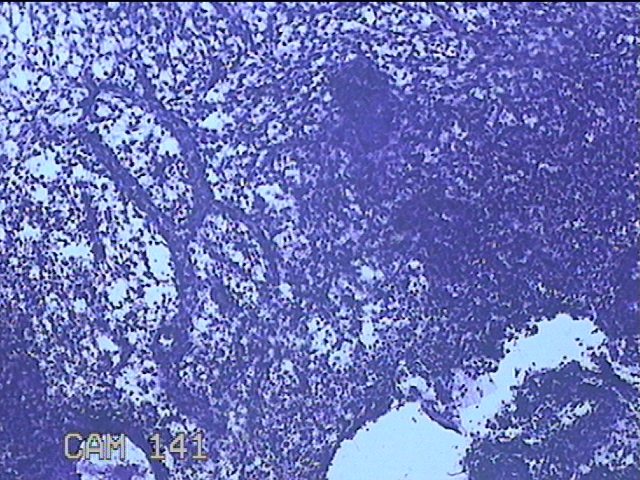

宫腔内容物

性别

女

年龄

37岁

临床诊断

1.右侧卵巢巧克力囊肿 2.异常子宫出血 3.子宫肌瘤 4.慢性子宫颈炎

一般病史

发现附件包块2年余。

标本名称

大体所见

灰白粉红色不规则碎组织4x2.3x1.3cm一堆。